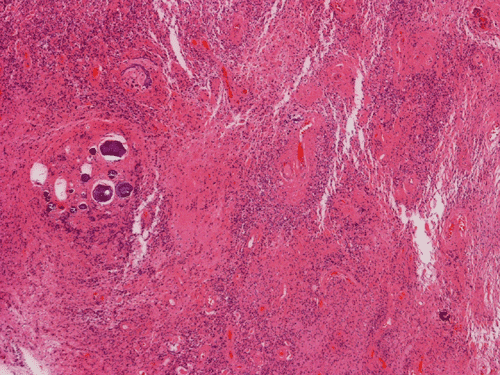

Pathology of the Case: MRI shows a large mass with the more solid component located in the lateral ventricles and the cystic component protruding into the cortical area. The solid area is enhanced (Panel A). On low magnification, the lesion has alternating area of high and low cellularity (Panel B) with scattered calcifications in some of the sections. Medium and high magnification demonstrates perivascular coronary arrangement of cytoplasmic processes (Panel C, D, and E). The nuclei are bland and mitotic figures are not readily seen. Randomly scattered brown pigment containing cells are found in multiple areas of the tumor (Panel F, G, and H). Scant lipidized cells with enlarged nuclei (Panel I) are also present. The tumor cells are strongly positive for glial fibrillary acidic protein (GFAP) (Panel J and K) and S100 protein but are negative for epithelial membrane antigen (EMA), neurofilament proteins, and NeuN. The overall Ki67 labeling is low but focal small areas (about the size of one high power field) has increased labeling. The pigment appears to be melanin on microscopic examination. These pigments are positive with Fontana-Masson stain (Panel L) but negative for Prussian blue stain for iron (Panel M). These features confirmed that these are melanin pigments. The pigment granules are positive for periodic acid-Schiff reaction (N), negative for Ziehl-Neelsen (acid fast) stain..

Microscopically, the histology of ependymoma can be quite variable and be easily confused with other gliomas. In essence, there are three major histologic features in ependymoma and most tumors contain a mixed features. The four features are perivascular radial arrangement of epdnymomal cells, isomorphic nuclei, ependymal rosettes or ependymal canals.

The diagnostic pattern of ependymoma is best visualized with very low magnification under the microscope. Similar to astrocytomas, the cytoplasm membrane cannot be discerned. The cells are poor in cytoplasm and the perivascular cell processes taper to a point around the blood vessels. Nuclear-free mantles form cuff like spaces around the vessels is an important diagnostic feature. These structures are also known as pseudorosettes. The cellularity in the cellular can be quite variable. The thickness of the perivascular paucinuclear zone can also be quite variable. As a result, they may be mistaken as astrocytoma easily and in the case of pediatric brain tumors as pilocytic astrocytomas.